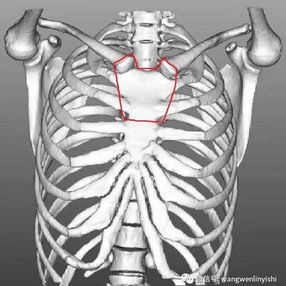

2. The upper portion of the sternum and the first and second ribs on each sides were excised, revealing that the ascending aorta, aortic arch were closely adjacent to the heart and sternum. Additionally, significant enlargement of the thymus was observed.

3. The thymus was excised and the anterior chest wall was reconstructed using a custom digital material tailored from the patient’s chest data. This ensured a clearance of about 2cm between the chest wall and the ascending aorta.

Flatback syndrome is an extremely rare spinal deformity characterized by a flattened thoracic spine and a loss of natural spinal curvature. This significantly narrows the space between the thoracic spine and the anterior chest wall, leading to a reduced volume of the chest cavity and compression of the mediastinum. Consequently, complications such as the displacement and compression of the heart, major blood vessels, and trachea may arise. Typically, while symptoms can be managed with conservative treatments, surgical intervention is required when these methods are proven to be ineffective.

However, now there is no effective surgical method to alter the shape of spine. In this case, chest wall reconstruction surgery offers a novel approach. This surgery involves shaping and reconstructing the entire chest wall, thereby pushing the anterior chest wall forward. By expanding the front-to-back diameter of the chest wall, this surgery alleviates pressure on the heart and other mediastinal organs.